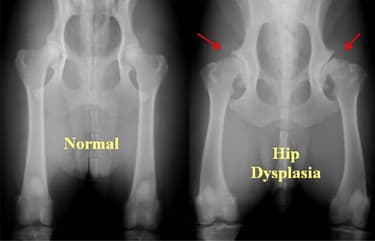

Dysplazie

Může být dědičná, ale také způsobena rychlým růstem štěňátka - vyšší hmotností, nesprávným pohybem i chybějícími minerály a vitamíny ve stravě.

Podezření na dysplazii či jiné ortopedické problémy vždy konzultujte se svým veterinářem. Dysplazie je diagnostikována pomocí RTG snímků ve správné poloze psa. Varovné signály by měly být: snížená aktivita, problémy se vstáváním, nechuť k pohybu.

Léčba je možná, avšak i přeléčený jedinec by neměl být použit v chovu. Používají se konzervativní metody jako fyzioterapie, protizánětlivé léky, kontrola hmotnosti. Chirurgická léčba dle stádia DKK a stáří psa.